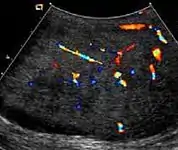

At ultrasound, the findings of acute epididymitis include an enlarged hypoechoic or hyperechoic (presumably secondary to hemorrhage) epididymis [Fig. 20a]. Other signs of inflammation such as increased vascularity, reactive hydrocele, pyocele and scrotal wall thickening may also be present. Testicular involvement is confirmed by the presence of testicular enlargement and an inhomogeneous echotexture. Hypervascularity on color Doppler images [Fig. 20b] is a well-established diagnostic criterion and may be the only imaging finding of epididymo-orchitis in some men.

Doppler ultrasound of epididymitis, seen as a substantial increase in blood flow in the left epididymis (top image), while it is normal in the right (bottom image). The thickness of the epididymis (between yellow crosses) is only slightly increased (7 mm).

Doppler ultrasound of the scrotum of the same case, in the axial plane, showing orchitis (as part of epididymo-orchitis) as hypoechogenic and slightly heterogenic left testicular tissue (right in image), with an increased blood flow. There is also swelling of peritesticular tissue.